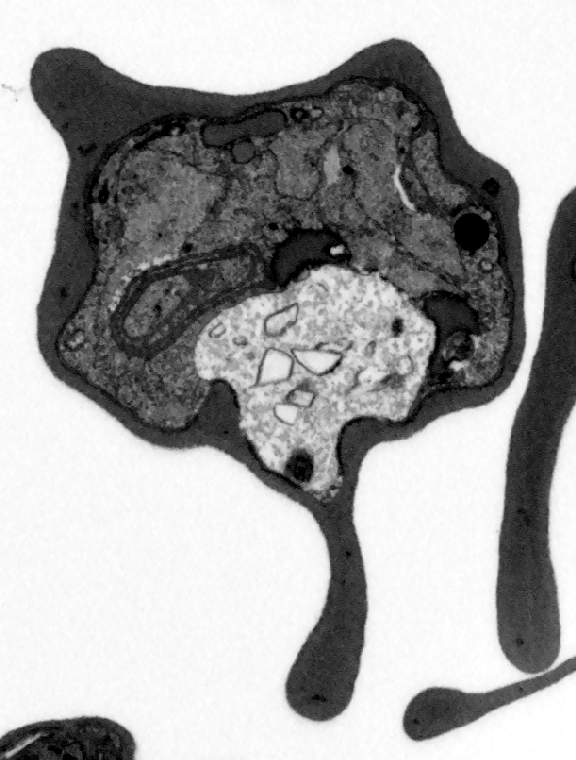

Actual z-index: 215Sampling: sampled from 427 source slicesScale: 10 x 10 x 20 nmContrast: per slice auto. Each generated plane is normalized independently for visual inspection.Frame cache: warming 0/96Keyboard: ←/→ step, Home/End jump.